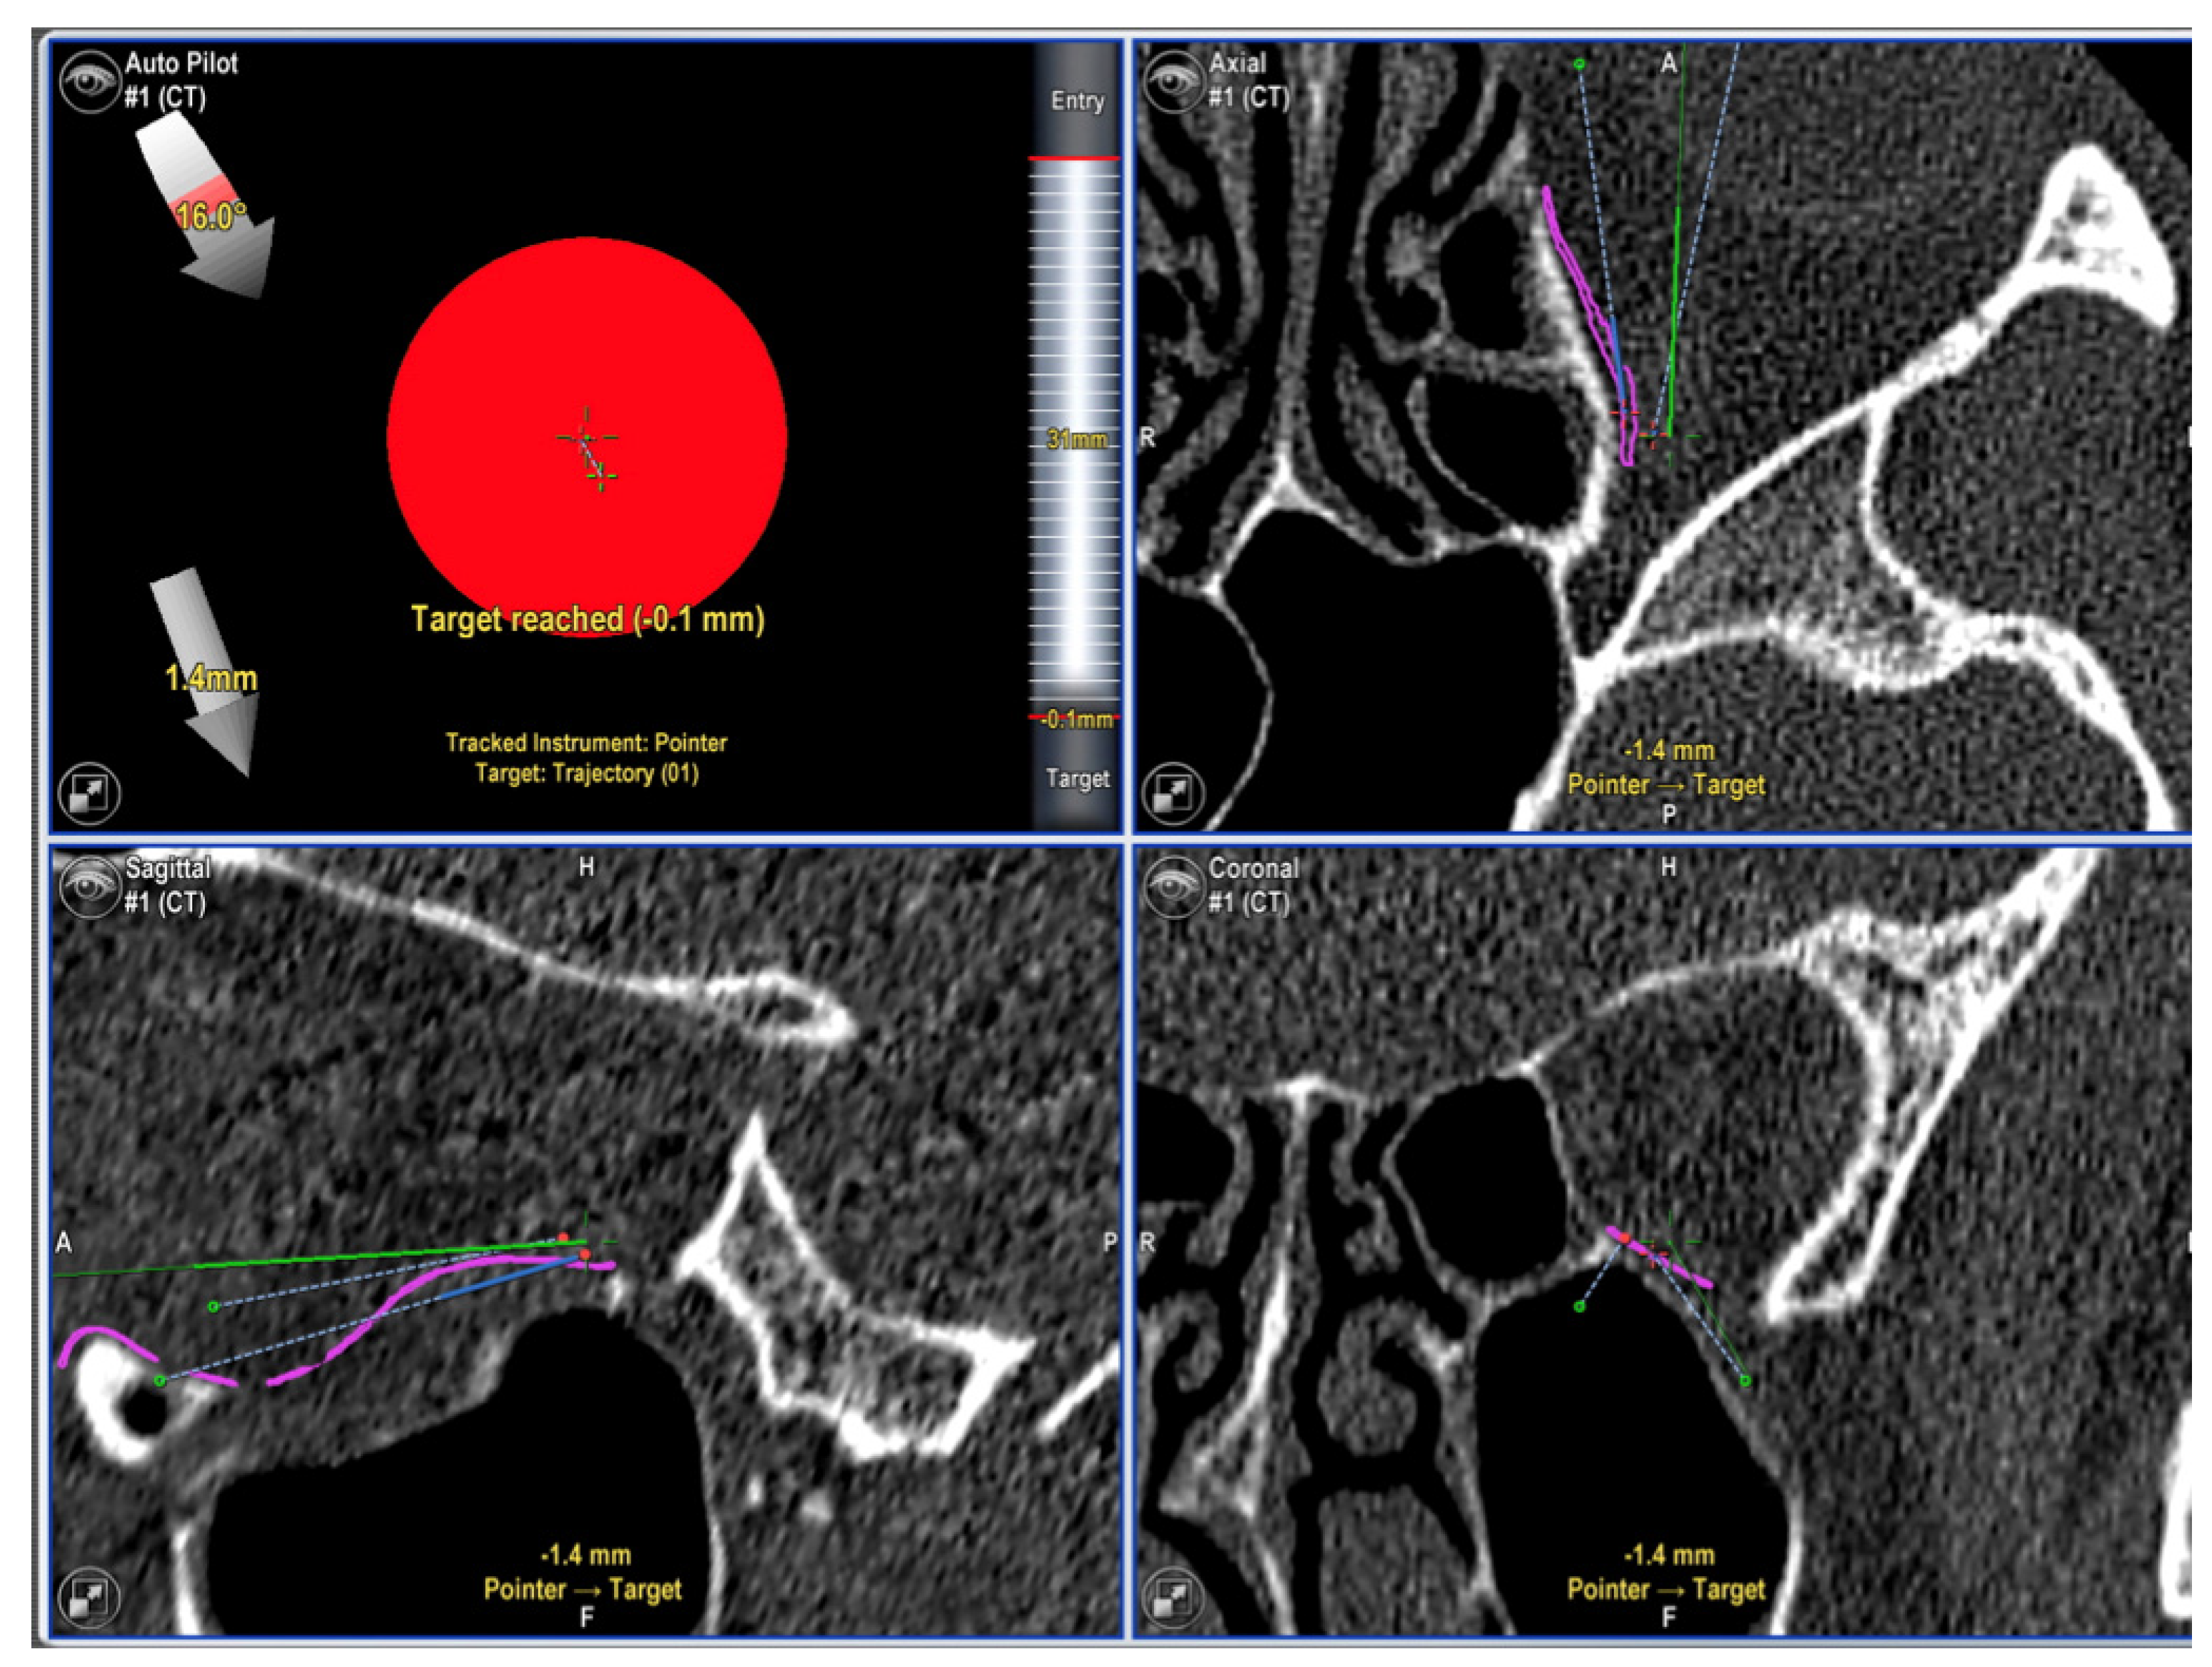

- Rana, M.; Chui, C.H.K.; Wagner, M.; Zimmerer, R.; Rana, M.; Gellrich, N.-C. Increasing the accuracy of orbital reconstruction with selective laser-melted patient-specific implants combined with intraoperative navigation. J. Oral Maxillofac. Surg. Off. J. Am. Assoc. Oral Maxillofac. Surg. 2015, 73, 1113–1118. [Google Scholar] [CrossRef] [Green Version]

- Schramm, A.; Suarez-Cunqueiro, M.M.; Barth, E.L.; Essig, H.; Bormann, K.-H.; Kokemueller, H.; Rücker, M.; Gellrich, N.-C. Computer-assisted navigation in craniomaxillofacial tumors. J. Craniofac. Surg. 2008, 19, 1067–1074. [Google Scholar] [CrossRef]